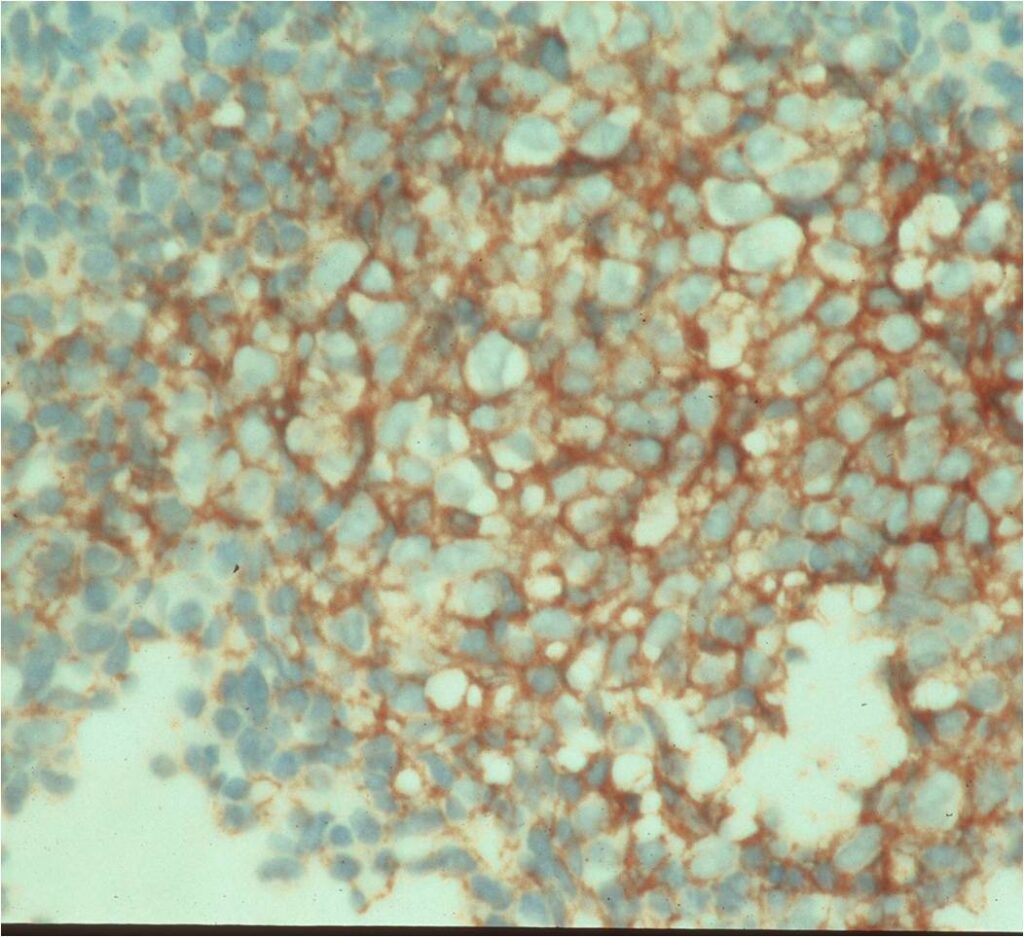

- Immunostains: Vimentin (+), CD99 (+); Leukocyte Antigen Negative

- Overexpress MIC2 detected by CD99

- Does not express neuroectodermal antigens